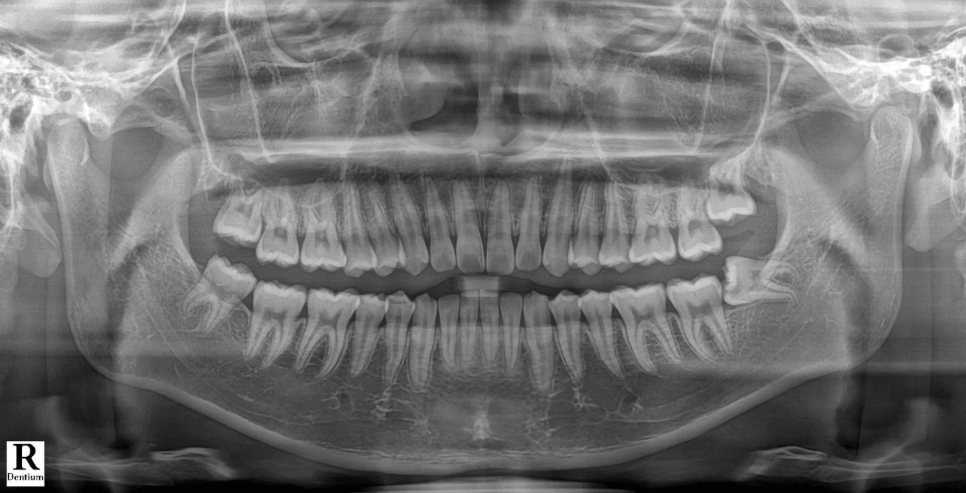

사랑니가 썩어있었기 때문에 뽑아야했지만,

사랑니 뿌리 끝과

중요한 하치조신경관이 가까워

CBCT를 찍어 분석했는데

다행히 문제가 없어 보여서

발치를 하기로 했었는데요